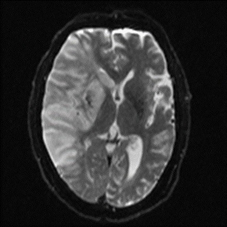

圖二、單側中大腦動脈缺血性腦中風

缺血性腦中風是「各種原因會造成局部腦組織灌流不足,引致腦組織功能異常或壞死」。缺血性腦中風常造成中度以上殘障後遺症,使病人失去工作能力。

目前對3小時內發作急性缺血性腦中風有正面療效的藥物是靜脈血栓溶解劑 (rt-PA)。但此類藥物主要副作用會造成體內出血併發症,而且此藥物使用在發病超過3小時後,其出血併發症的風險隨著給藥時間延遲急遽增高,因此使用此藥物必需經由專科醫師判斷符合「適應症」及排除「禁忌症」才能使用。另外有一部份腦中風病人可以考慮動脈血栓移除術來「打通堵塞的血管」、但這類處置存在高風險,必需謹慎評估個案是否符合適應症。所以對疑似急性腦中風發病民眾來說,就是儘快聯絡救護車,最好能於3小時內抵達具備臨床評估急性腦中風、施行血栓溶解劑治療,及動脈血栓移除術的醫院急診接受診治。